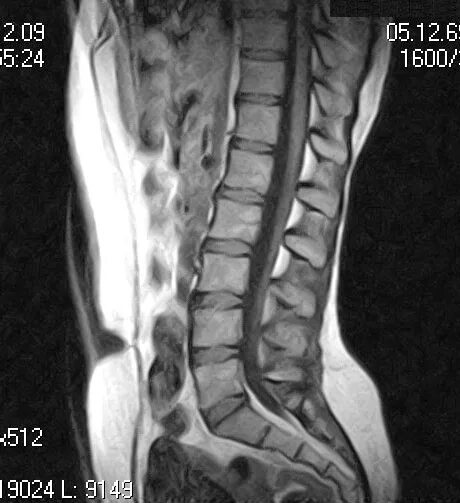

Перед мрт позвоночника можно кушать